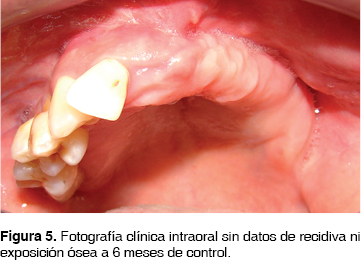

Se inicia manejo con clindamicina 600 mg IV cada 8 h y ceftriaxona 1 g IV cada 12 h. A continuación, bajo anestesia general inhalatoria balanceada, se realiza hemimaxilectomía subtotal, mediante abordaje circunvestibular durante el procedimiento se observan áreas óseas líticas y necróticas (Figura 4) , se procede a la resección de la lesión obteniendo un espécimen quirúrgico de 2 x 4 cm. Se sutura con ácido poliglicólico 3 ceros. Se envía la pieza quirúrgica a patólogo oral que reporta osteomielitis crónica maxilar con bordes libres de lesión, continúa durante 30 días con penicilina G procaínica 800,000 UI IM cada 24 h por 30 días. En la actualidad se encuentra clínica e imagenológicamente sin datos de recidiva (Figuras 5 y 6).